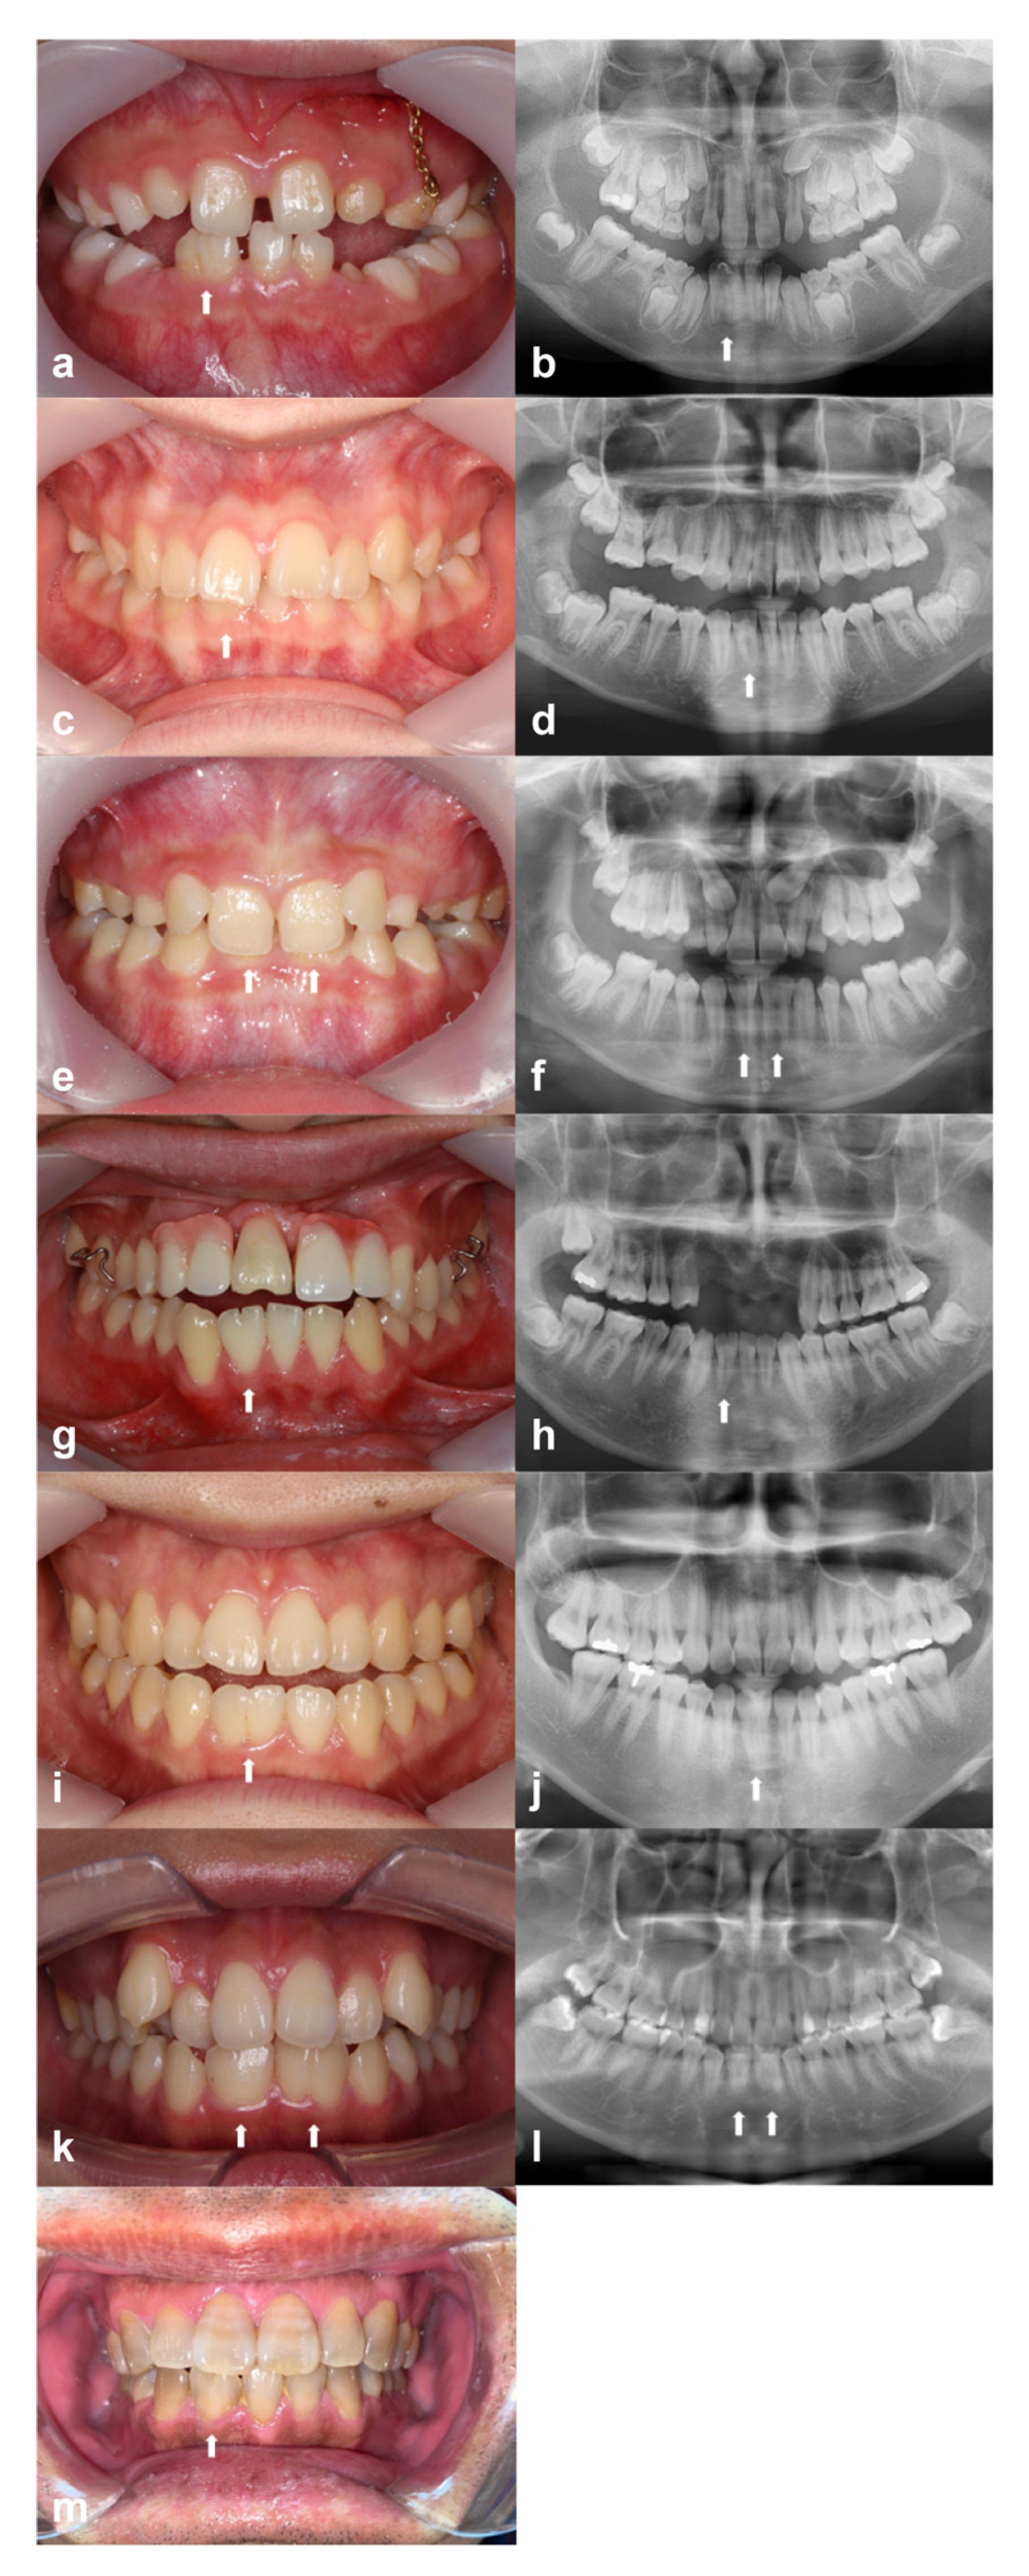

Figure 1 shows the six family trees. Figure 2 shows intraoral photographs and panoramic radiographs of the patients with fused teeth. Table 1 summarises patient sex, the positions of the fused teeth, and the inclusion type (monoliteral or bilateral).

Figure 2.

Intraoral and panoramic radiographs, respectively, of: (a,b) patient A-1 (Family A); (c,d) patient B-1 (Family B); (e,f) patient C-1 (Family C); (g,h) patient D-1 (Family D); (i,j) patient E-1 (Family E); (k,l) patient F-1 (Family F); (m) intraoral photograph of patient F-2 (Family F). White arrows indicate fused teeth.